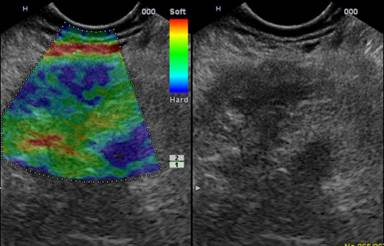

A 53-year-old man affected by multiple sclerosis referred to us for suspected intestinal sub-occlusion. Physical examination showed abdomen tense, with diffuse pain to deep palpation. Laboratory evaluation, abdominal ultrasound and X-ray were normal. A contrast-enhanced CT revealed a marked thickening of duodenal walls with enlargement of the head of the pancreas, with no certain cleavage plane with the duodenum. The pancreatic body presented a solid area of 4 cm of diameter. Upper gastrointestinal endoscopy was performed, revealing duodenal sub-stenosis, with mucosal hyperemia and edema (Figure 1). Biopsies established a diffuse Brunner’s gland hyperplasia without any sign of neoplasia (Figure 2). Therefore, EUS was performed and showed, at the sub-stenosis of the duodenum, a hypoechoic thickening wall with loss of normal stratification extending to muscularis and which seemed infiltrate the pancreatic parenchyma (Figure 3). Multiple lymph nodes near the pancreas were described. The body of the pancreas appeared diffusely heterogeneous and inside it and close the superior mesenteric artery, was observed a hypoechoic area of 4.3 cm of diameter with irregular margins, that showed a stiff consistency to the elastosonography (Figure 4). FNA of this lesion was performed and the cytological analysis showed signs of acute and chronic pancreatitis with no evidence of malignancy (Figure 5). The suspicion of malignancy was very high (according to radiological and endoscopic images), so we repeated upper gastrointestinal endoscopy with biopsies and EUS-FNA showing only a diffuse Brunner’s glands hyperplasia and cytological findings of pancreatitis. In view of clinical improvement, with gradual resolution of sub-occlusion and exclusion of malignancy we discharged the patient and decide to perform an endoscopic follow-up into three months. Three months after the patient was asymptomatic and on follow-up upper gastrointestinal endoscopy, duodenal sub-stenosis improved and histology confirmed Brunner hyperplasia.

Figure 4. Endoscopic ultrasound findings of hypoechoic area of the body of the pancreas harder than surrounding tissue on elastosonography. |